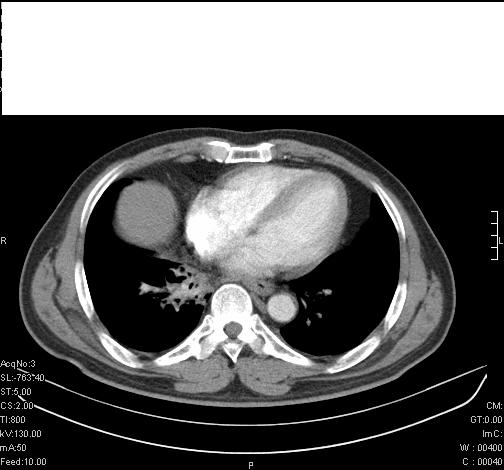

标题: CT6685:右肺阻塞性炎症,增强CT。

前几天,发了患者的平扫片,患者抗炎一周后增强扫描。右中叶病灶吸收明显,但下叶病灶未见明显吸收。右肺门可见结节影,看来凶多吉少

右肺下叶支气管管腔狭窄,管壁增厚,右下肺见斑片状高密度影,考虑右侧肺门中心肺癌伴阻塞性肺炎

右肺下叶支气管壁明显增厚,考虑癌症并阻塞性炎症、肺门淋巴结肿大

考虑右肺癌并阻塞性炎症、肺门淋巴结肿大

右肺下叶支气管壁不规则增厚,右肺下叶有斑片状影分布。考虑右肺中央型肺癌伴右肺下叶阻塞性改变。建议支纤镜检查。平扫比增强较好显示了病变情况。

右主支气管狭窄,管壁增厚。考虑右中心性肺ca伴阻塞性肺炎。

既然抗炎治疗有效,可继续治疗;右肺下叶支气管管腔狭窄,管壁增厚,右下肺见斑片状高密度影,右侧主支气管后见结节影(淋巴结?),肺癌不能排出。